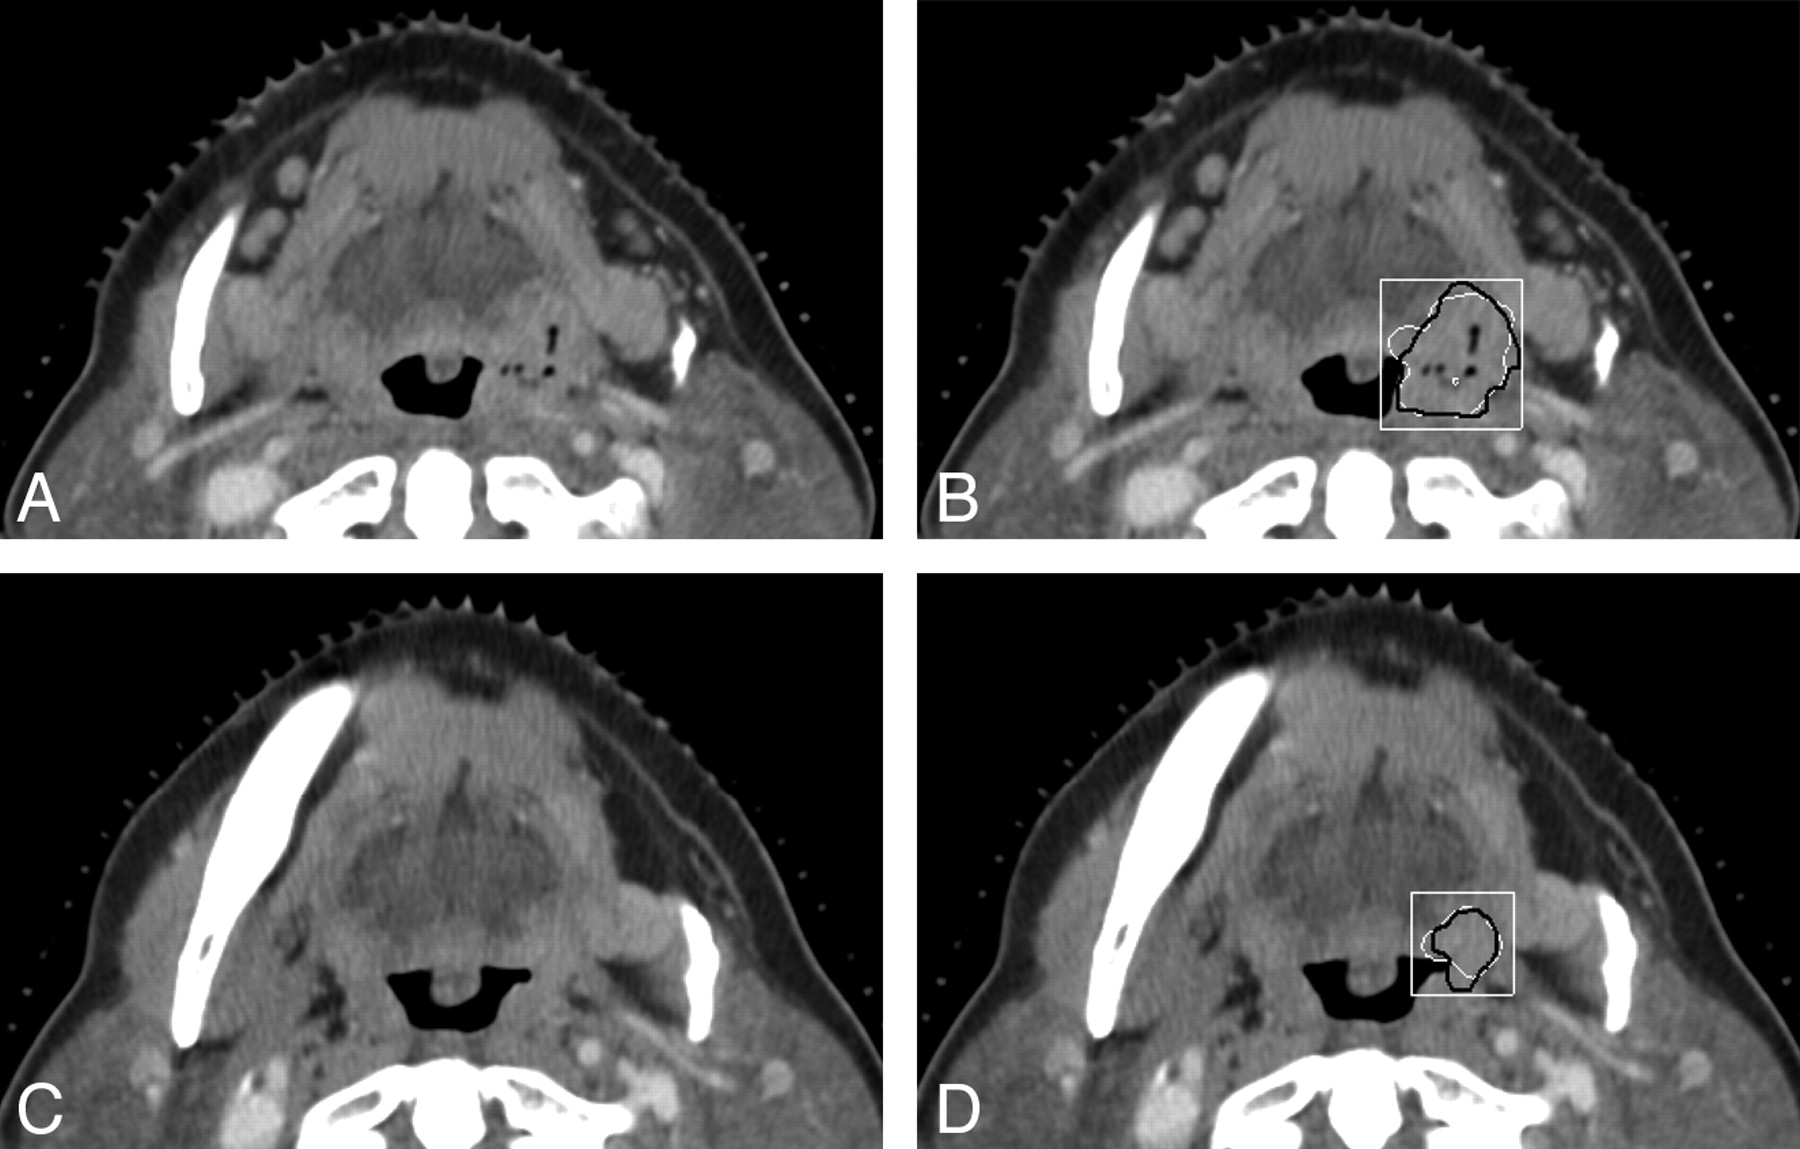

Examples of the computerized 3D level-set segmentation of the primary head and neck carcinomas on pre- and post-treatment CT scans are shown in Figs 1 and 2 for a necrotic tonsil carcinoma and a heterogeneous tongue carcinoma, respectively. In both figures, the radiologist's hand-drawn bounding box used for the automatic segmentation is also shown.

CT sections of a tonsil carcinoma on pre- and posttreatment CT scans. The carcinoma is necrotic on the pretreatment scan. This is also a subtle lesion (difficulty rating = 4 for the posttreatment scan) in the dataset. A and B, An axial section on the pretreatment scan (A), the automatic segmentation (white contour, B), and the reference-standard (hand-drawn) segmentation (black contour, B) superimposed on the pretreatment scan. C and D, An axial section on the posttreatment scan (C), the automatic segmentation (white contour, D), and the reference-standard segmentation (black contour, D) superimposed on the posttreatment scan. The radiologist's hand-drawn bounding box (white rectangle) used for the automatic segmentation is also shown in B and D. The lesion is shown on the best section marked by the radiologist for each scan.

The segmentation system performed well in some of the lesions visually judged to be most difficult by radiologists. Figure 1 shows a subtle necrotic tumor with a difficulty rating of 4, which was accurately segmented by the computer system on both the pre- and the posttreatment scans compared with the manual outlines. Although most of the boundaries between the lesion and the adjacent normal tissues had low contrast, the preprocessing in combination with the level-set method was able to find reasonable boundaries in this case.